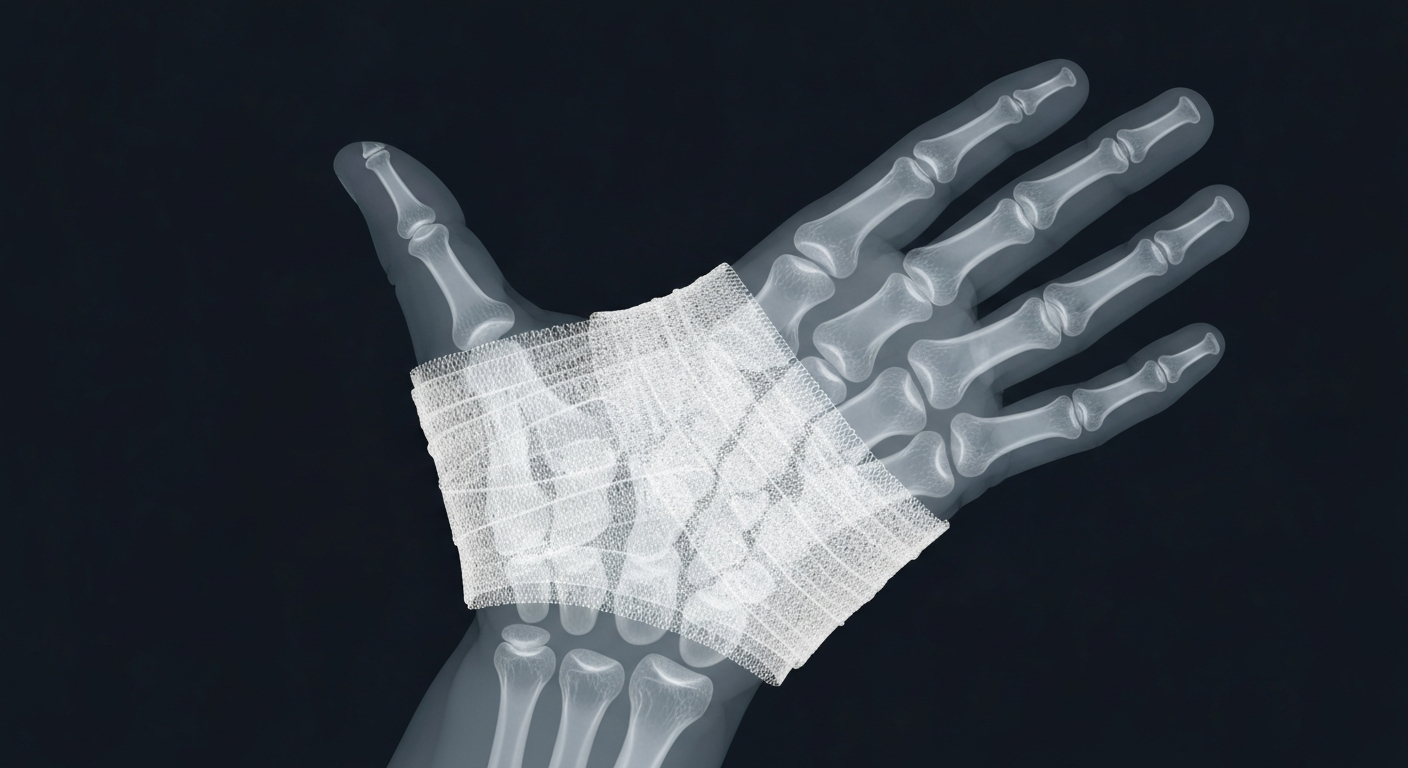

An X-ray view exposes the internal structure of a bandaged hand, underscoring the importance of sterile, contaminant-free wound care products.Santa Fe Springs TodayBlaine Labs, Inc., a pharmaceutical company based in Santa Fe Springs, California, has issued a voluntary nationwide recall of several of its wound care gel products due to potential microbial contamination. The recall affects multiple product lots that were distributed across the United States.